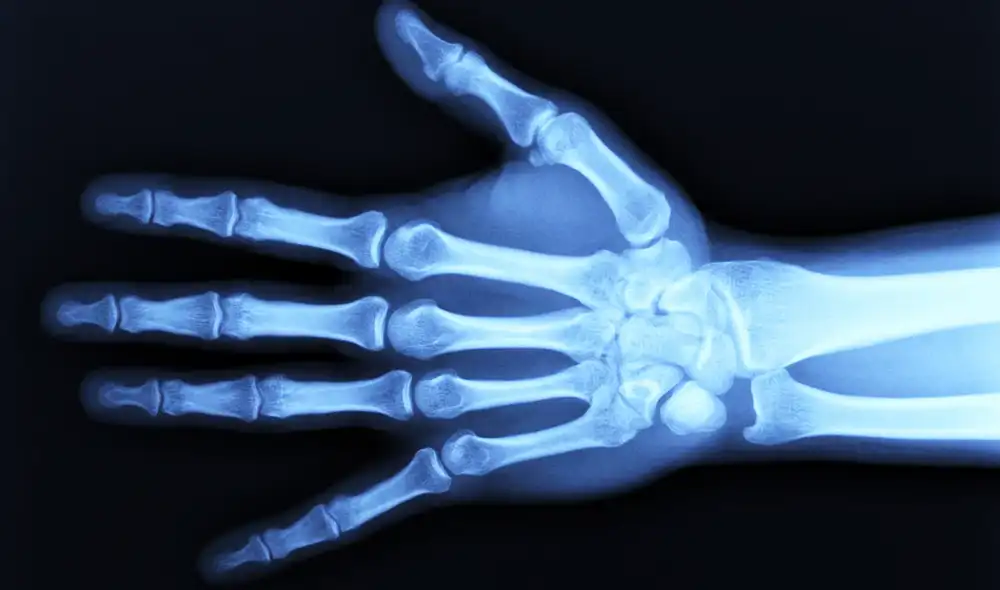

Científicos de la Universidad Tecnológica de Kaunas, Lituania, presentaron una alternativa novedosa para abordar el daño del cartílago, uno de los principales problemas asociados a la osteoartritis. El estudio analizó el uso de partículas microscópicas liberadas por células de la sangre menstrual, conocidas como vesículas extracelulares, y comprobó su capacidad para estimular procesos de reparación en tejidos afectados.

El estudio publicado en Nature se centró en vesículas extracelulares obtenidas de células estromales mesenquimales presentes en la sangre menstrual. Estas estructuras actúan como mensajeros biológicos que transportan señales capaces de modificar la actividad de otras estructuras, incluida su capacidad de regeneración. Estas partículas pueden ingresar a las células del cartílago y activar procesos que favorecen su recuperación o disminuyen la inflamación.

Los experimentos incluyeron muestras de tres donantes sanas y tejido de 10 pacientes con osteoartritis sometidas a cirugía. Los resultados mostraron efectos positivos incluso en células de mujeres postmenopáusicas, cuyo potencial regenerativo suele ser limitado. En estos casos, las vesículas no solo mejoraron la función, sino que también redujeron el deterioro del tejido e incrementaron la expresión de receptores de progesterona, un factor clave en la respuesta biológica del cartílago.